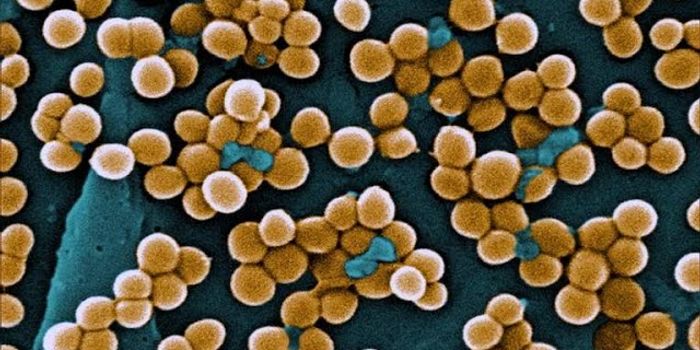

NOV 09, 2017VideosThe antibiotic resistance crisis has threatened the treatment and prevention of infections caused by bacteria, viruses a ...

DEC 07, 2017VideosAntibiotic resistance is a problem that could affect the health of thousands. From overuse of antibiotic drugs, some bac ...